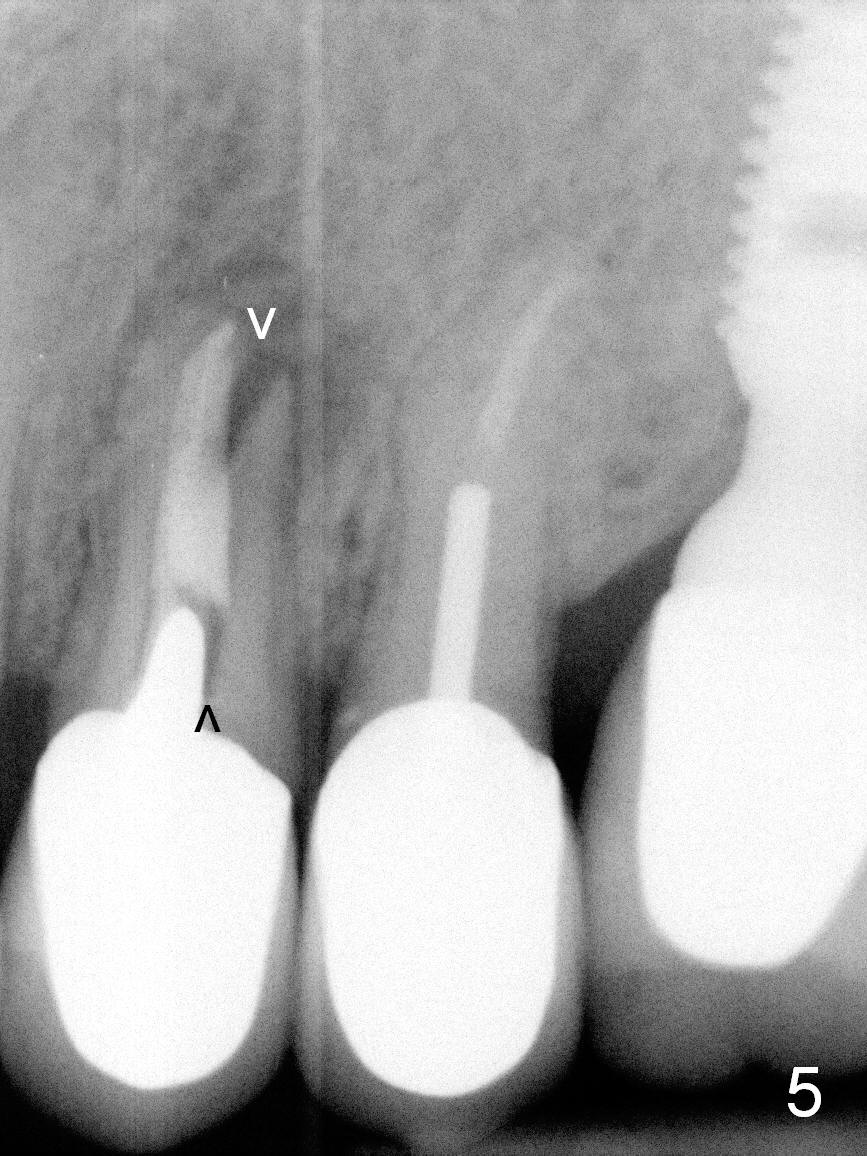

A 57-year-old lady had poor dentition, including periapical radiolucency of the tooth #12, 8 years ago (Fig.1 *, 2007).  After comprehensive treatment, the pathology is apparently under control (Fig.2 <, 2011).  CBCT shows the pathology not completely resolved (Fig.3,4, coronal section, 2012).  Early this year, there was sign of crack tooth at #12 (Fig.5 arrowheads).  Last Saturday she returned because of dislodgement of the crown and post.  The tooth is found to be non salvageable.

A 4.5x14 mm bone-level or 4.5x17 mm tissue-level implant appears to be appropriate for the site according to the PA (Fig.6,7).  CBCT shows that there is enough bone to place a 4.5x20 mm tissue-level implant (Fig.8).  This is more appropriate, considering the large radiolucency (Fig.5), the age of the patient (possibly osteoporosis), and the maxilla (bone softer than that of the mandible).  The implant will be supported by approximately 8 mm solid bone apically (Fig.8).